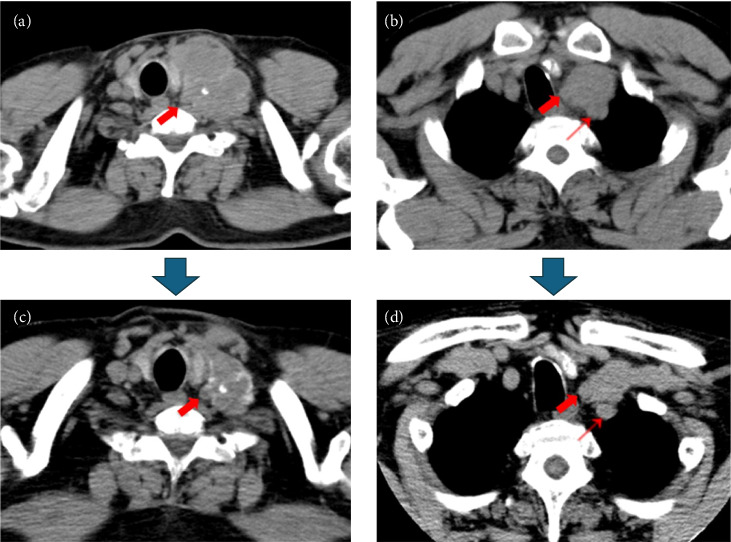

A 65-year-old male presented to our hospital with a complaint of a left cervical mass. The left supraclavicular lymph node was enlarged, measuring 77 mm, and biopsy results confirmed metastasis of papillary thyroid carcinoma (PTC). The left supraclavicular lymph node extended to the upper mediastinum and invaded the internal jugular and subclavian veins, with suspicion of common carotid and subclavian artery invasion. Surgical resection was deemed infeasible. The Oncomine Dx Target Test system, a gene panel test using a next-generation sequencer, of the metastatic lymph node was positive for RET fusion (CCDC6-RET), and selpercatinib treatment was initiated. After 4 months, the tumor reduced in size, and surgery was performed. The postoperative course was uneventful, with ongoing follow-up. This case is a successful case of neoadjuvant chemotherapy for RET fusion-positive PTC with local regional progression.